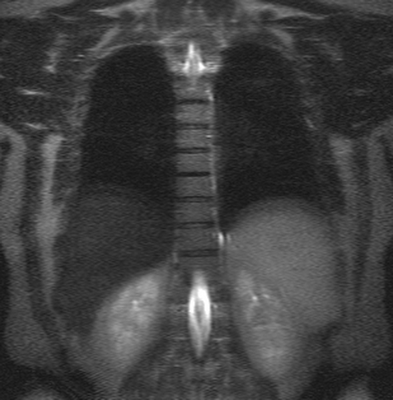

Множественные (2) гемангиомы на МРТ грудного отдела позвоночника

Грудной отдел позвоночника на МРТ в коронарной проекции